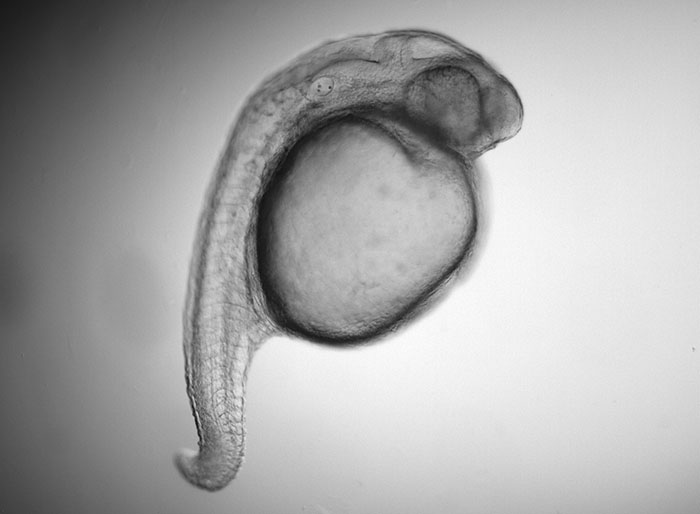

Much is known about genes that are required for normal embryonic development, but how chemicals in the environment influence these genes to cause congenital anomalies (also called birth defects) is less well understood. An estimated 6% of babies worldwide are born with a congenital anomaly (World Health Organization). Using genetic and pharmacologic approaches, we study how prescription drugs cause congenital anomalies at the molecular and cellular levels. We hope that our studies will make prescription drugs safer for pregnant women and reveal new and fundamental insights into human embryonic development.